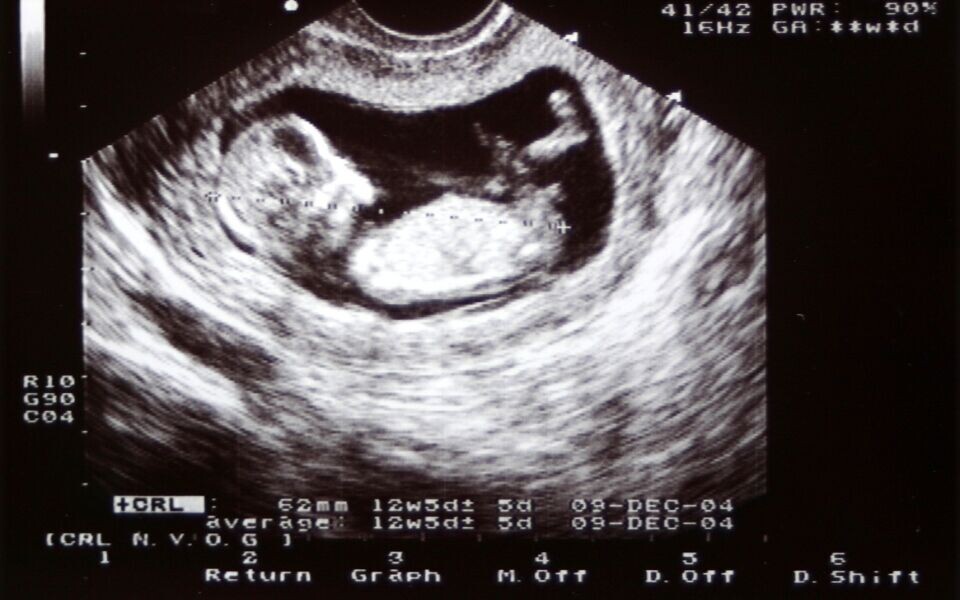

NIPT er en metode hvor man analyserer cellefritt foster-DNA i den gravides blod. Testen har høy spesifisitet og sensitivitet for påvisning av trisomi 21 (Downs syndrom), 18 og 13. Direktoratet ønsker å tilby NIPT som en risikofri sekundærtest til gravide som har høy estimert trisomirisiko etter kombinert ultralyd og blodprøve i uke 12 (KUB-test).

Dagens sekundærtest er fostervannsprøve eller morkakeprøve. Men slike invasive undersøkelser innebærer 0,5 - 1 prosent risiko for spontanabort. Direktoratet mener det er etisk og medisinskfaglig problematisk å ikke tilby NIPT som alternativ sekundærtest til kvinner som uansett har rett til fosterdiagnostikk etter dagens norske regelverk.